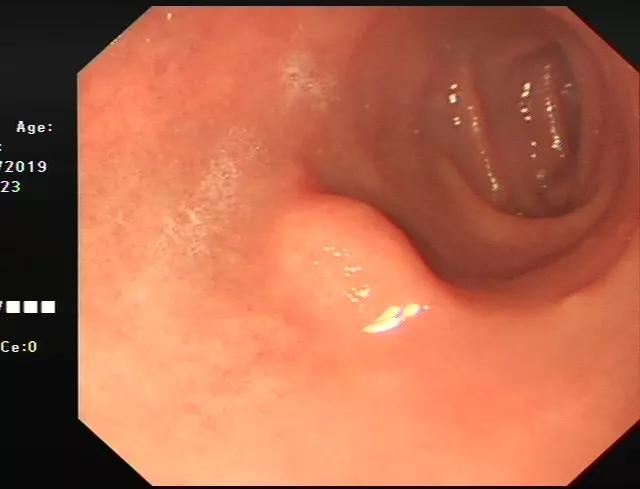

比如我们发现了十二指肠一个粘膜下隆起(下图),但是无法判断他的性质。

通过超声内镜,我们可以看出它在哪一层,是什么结构、什么性质。见下图: